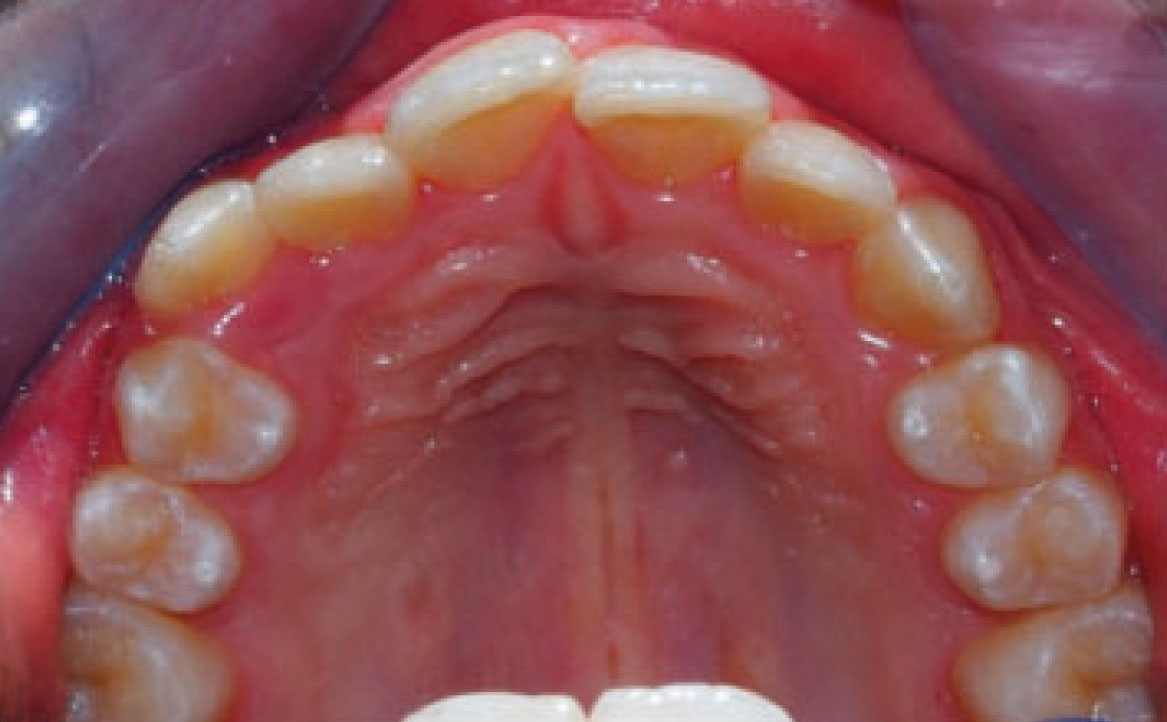

Dall’esame obiettivo intra orale si osservava una seconda classe canina destra e sinistra, una seconda classe molare destra e sinistra, e un diametro inter-canino e inter-molare ridotto sia in riferimento al mascellare superiore sia al mascellare inferiore (fig. 3A-3E).

Al fine di ottenere un’espansione delle arcate, nella fase iniziale, è stato posizionato un espansore rapido palatale sull’arcata superiore e un arco linguale a livello dell’arcata inferiore per permettere le estrazioni dei denti decidui compromessi.

Terminata la prima fase, all’età di 11 anni, il paziente è stato rivalutato tramite gli esami radiografici. Dall’OPT si osservava la presenza della dentatura permanente, con prossima esfoliazione dei settimi, oltre alla formazione delle gemme degli elementi 18-28-38-48 (fig. 4).

Clinical examination revealed high caries risk, poor oral hygiene, and constricted upper and lower arches.